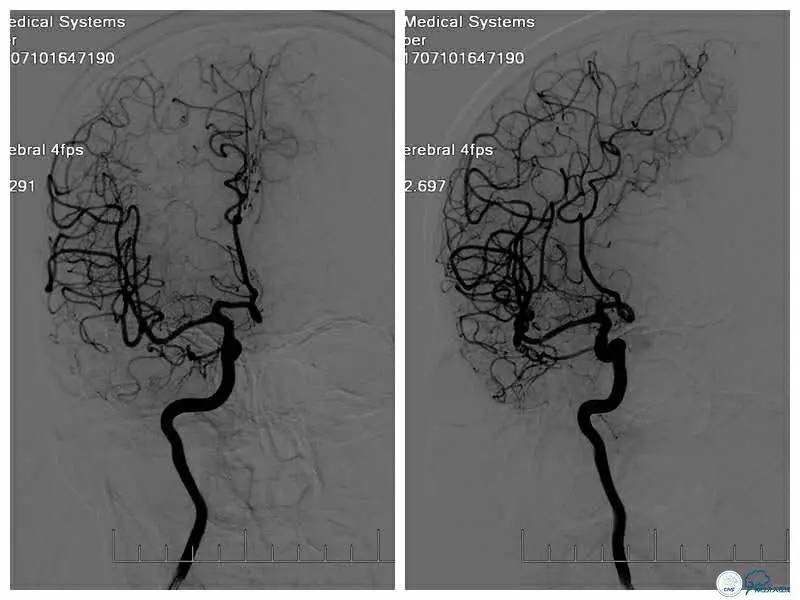

对比术后半年和术前及术后第二天的TCD显示(图5):原右大脑中动脉血流低平,频谱圆钝;术后第二日血流速度较术前明显增快,搏动指数增高,频谱形态未见明显异常;术后半年显示右大脑中动脉血流速度及频谱形态基本正常。